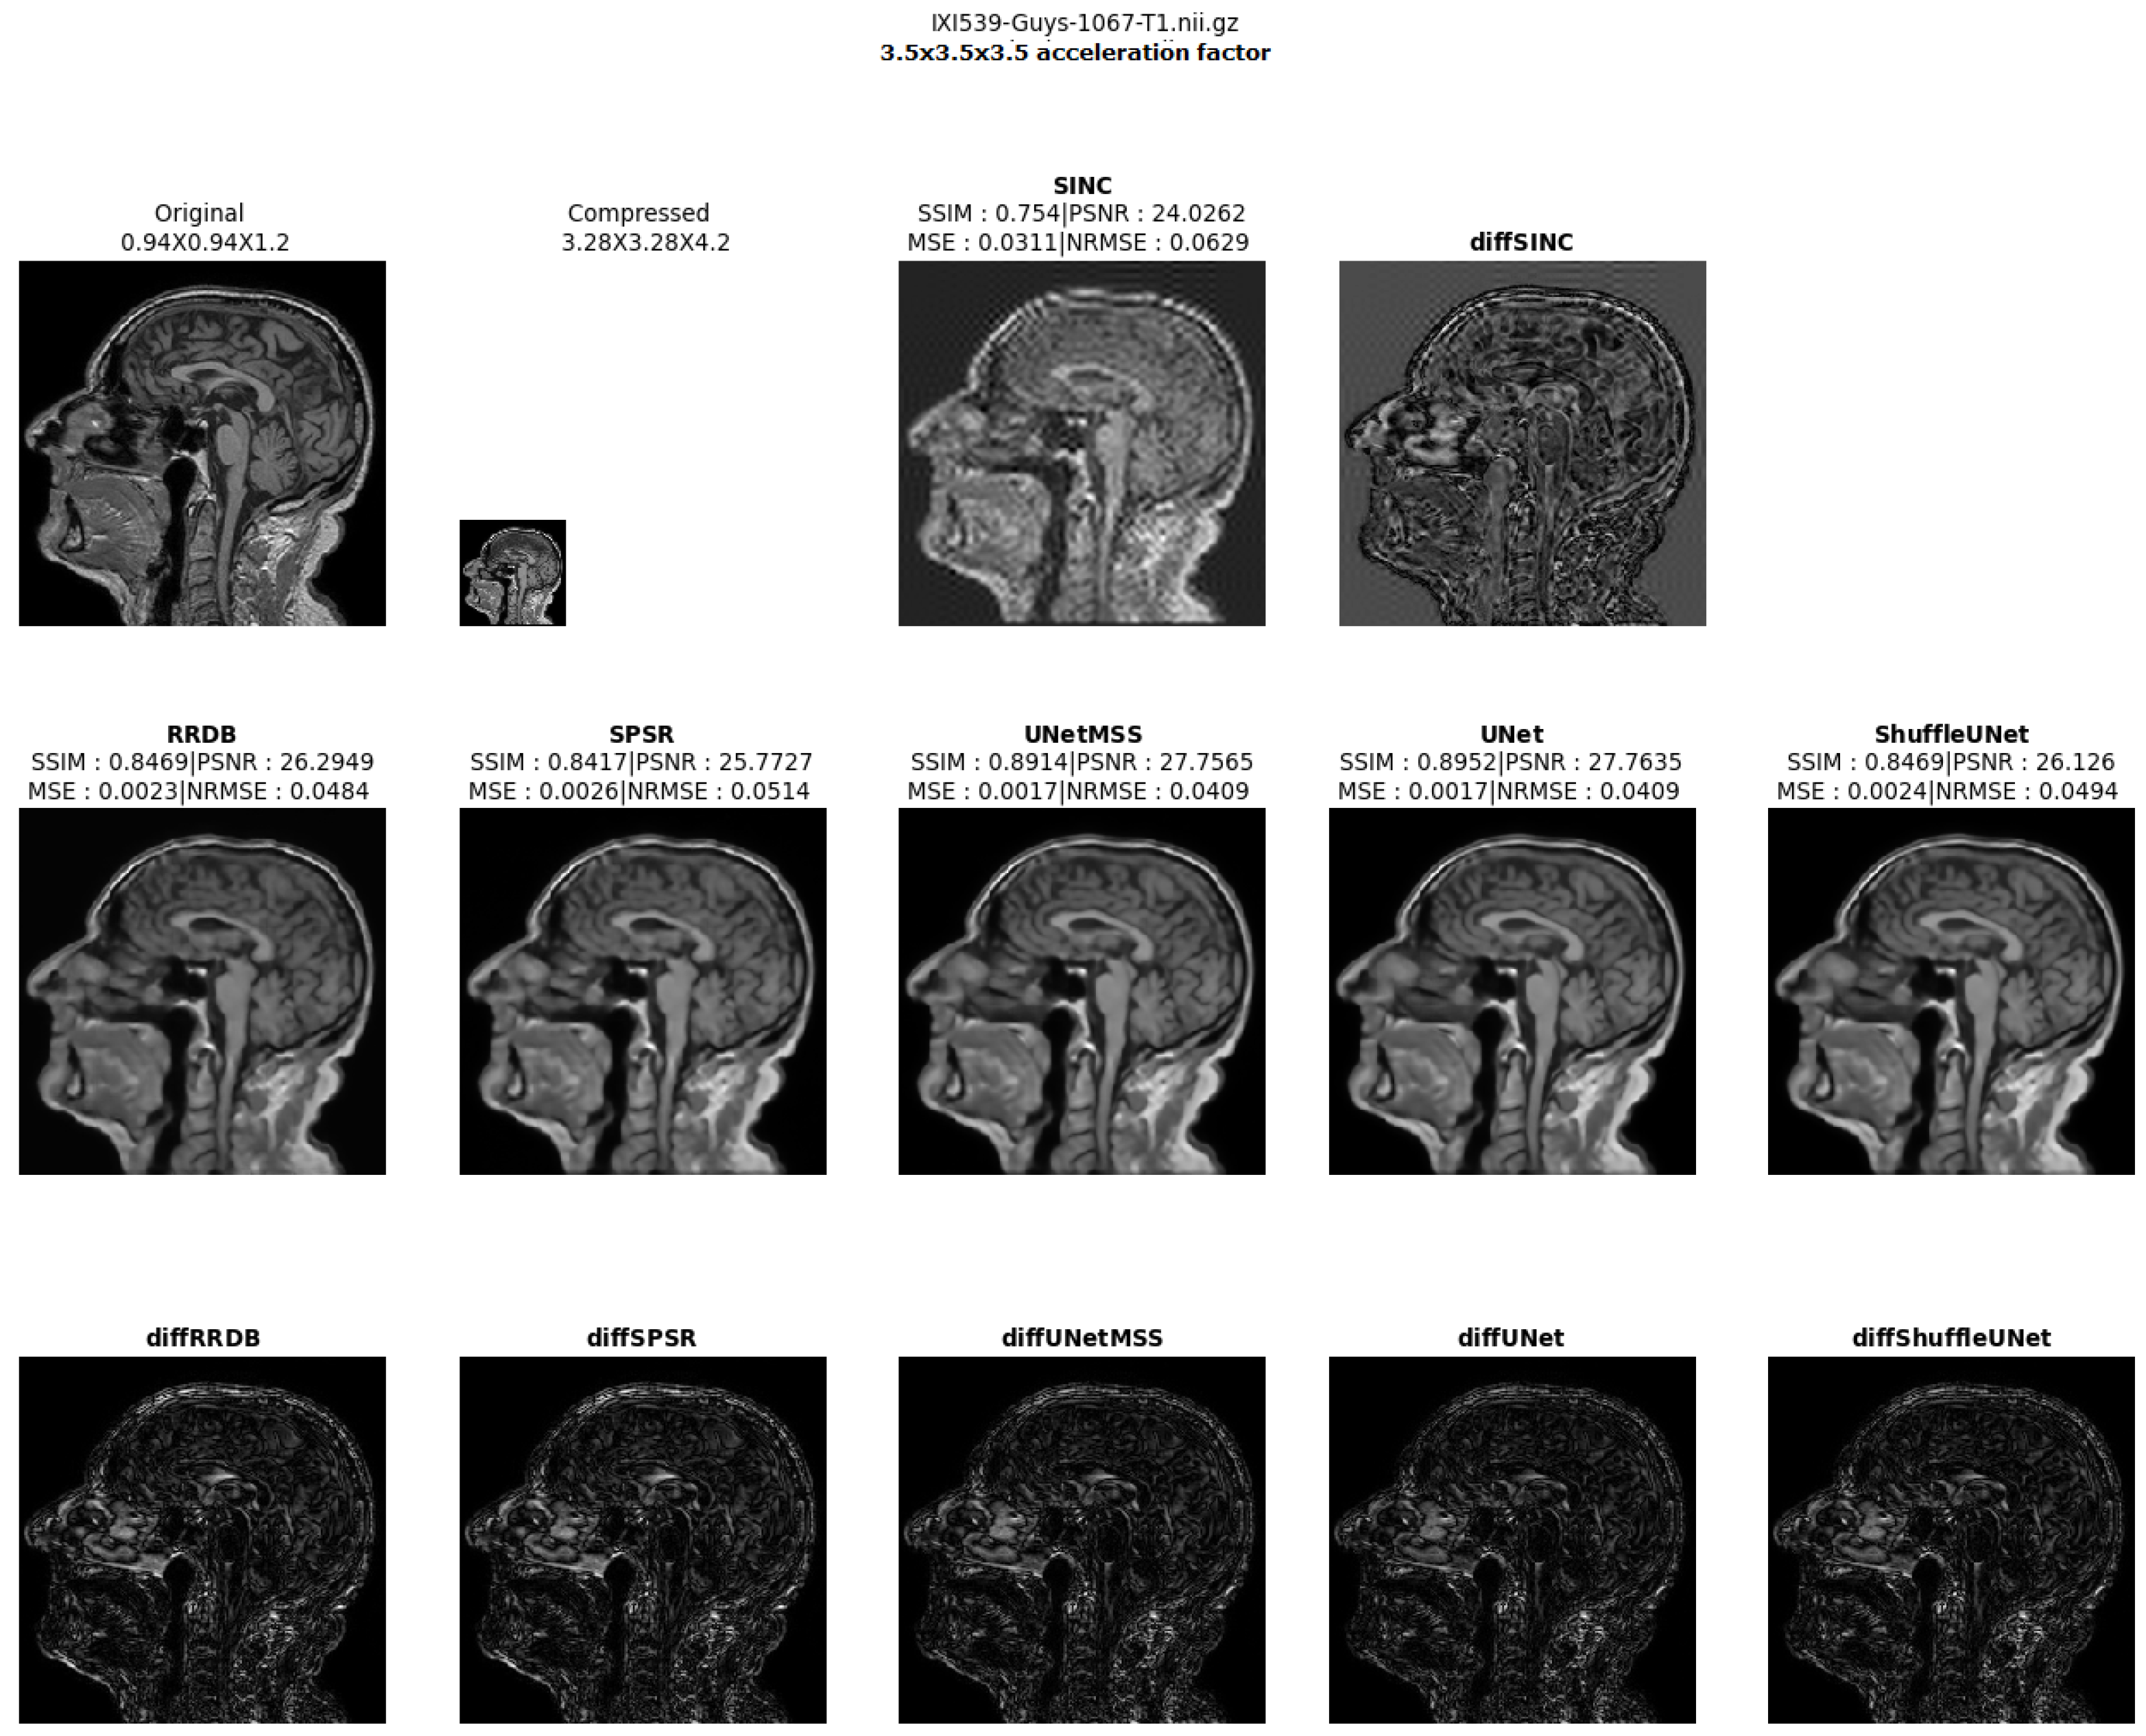

- Visualising individual model results for all the acceleration factors.

Different 3D CNN Models Results Comparison for Cross Acceleration Factor of IXI-T1 Dataset